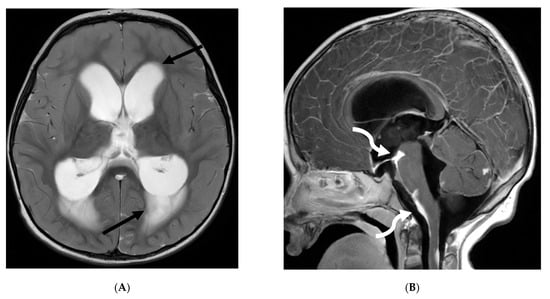

Moya moya disease (MMD) is a complex neurovascular condition characterized by progressive narrowing of the internal carotid terminus and/or the proximal anterior or middle cerebral arteries. Due to chronicity, arterial collateral vessels develop to bypass the narrowing. These collaterals can be basal, leptomeningeal or transdural, arising from perforating arteries, typically coursing through the meninges [90]. These collaterals are often small, weak, and prone to bleed or clot.

MRI, the standard noninvasive imaging modality, shows vascular narrowing on T2-weighted images and collateral vessels [91,92]. FLAIR sequence helps in detecting subtle areas of gliosis or chronic white matter ischemia. While DWI remains the optimal sequence for detecting acute ischemia, SWI helps in detecting acute or chronic microbleeds in addition to prominent deep medullary veins in areas with impaired blood flow (depicted as the “brush sign”). MR angiography defines the disease extent.

In children with moya moya, the LME is termed the “ivy sign” as the appearance resembles creeping ivy (Figure 18) [93]. LME arises due to two key factors in MMD, namely neovascularization and retrograde flow from congested pial vessels [94].

Figure 18.

Axial FLAIR (A), MRA (B), axial ASL perfusion (C) and axial T1 post contrast (D): 7-year-old girl with Down’s syndrome: Abnormal FLAIR hyperintense signal with LME along the right cerebral convexity sulci, predominantly in the frontoparietal region representing “ivy sign” (arrows). Asymmetric decreased perfusion in the right frontal and temporal regions (curved arrows). The M1 segment of right MCA is not visualized with extensive moyamoya vessels (dashed arrows). The M2 and M3 branches of right MCA are asymmetrically attenuated. Bilateral A1 segments are not identified with extensive collateralization and diminutive caliber of A2 and A3 segments (arrow heads).

Although LME is a supportive feature in the diagnosis of moya moya, LME is a marker of collateral vessel status and less LME is a marker of severe clinical symptoms and poor postoperative outcomes [95]. In addition, degree of reduction of LME after surgery has been proposed to be a marker of effective surgery [96].